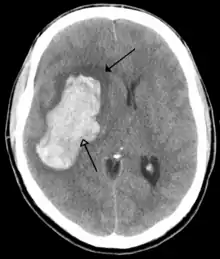

Tumours

Brain tumours can be either benign or cancerous. Most malignant tumours arise from another part of the body, most commonly from the lung, breast and skin.[177] Cancers of brain tissue can also occur, and originate from any tissue in and around the brain. Meningioma, cancer of the meninges around the brain, is more common than cancers of brain tissue.[177] Cancers within the brain may cause symptoms related to their size or position, with symptoms including headache and nausea, or the gradual development of focal symptoms such as gradual difficulty seeing, swallowing, talking, or as a change of mood.[177] Cancers are in general investigated through the use of CT scans and MRI scans. A variety of other tests including blood tests and lumbar puncture may be used to investigate for the cause of the cancer and evaluate the type and stage of the cancer.[177] The corticosteroid dexamethasone is often given to decrease the swelling of brain tissue around a tumour. Surgery may be considered, however given the complex nature of many tumours or based on tumour stage or type, radiotherapy or chemotherapy may be considered more suitable.[177]

Some treatments for stroke are time-critical. These include clot dissolution or surgical removal of a clot for ischaemic strokes, and decompression for haemorrhagic strokes.[195][196] As stroke is time critical,[197] hospitals and even pre-hospital care of stroke involves expedited investigations – usually a CT scan to investigate for a haemorrhagic stroke and a CT or MR angiogram to evaluate arteries that supply the brain.[194] MRI scans, not as widely available, may be able to demonstrate the affected area of the brain more accurately, particularly with ischaemic stroke.[194]